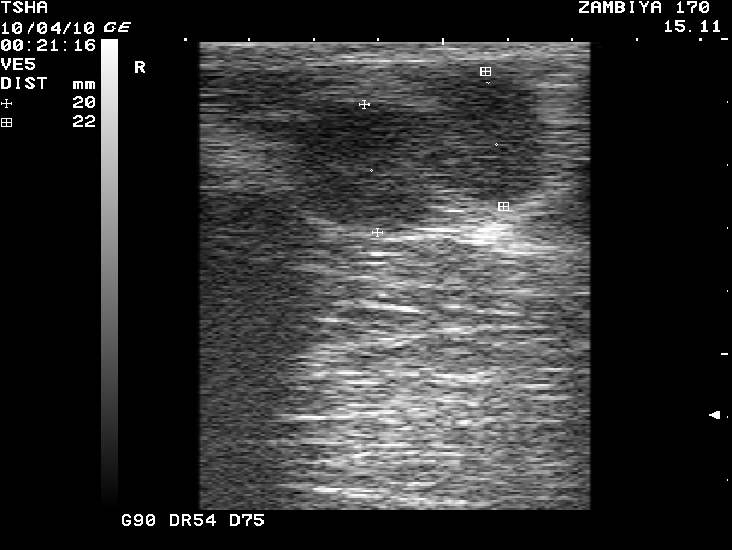

Рис. 3. Особенности восстановления овариальной функции у коровы Замбия 170 с фолликулярной кистой правого яичника. Овулин вводили 23.01.10 и 6.02.10. После первой гормональной обработки зафиксировали формирование фолликулярной кисты де ново в левом яичнике, после второй - формирование двух кистозных желтых тел в правом яичнике. Корова плодотворно осеменена в на 46 день от начала лечения (32 день после второй гормональной обработки).

Пример отрицательного овариального ответа на овулин после первого курса гормонотерапии и восстановления овуляции после его повторного применения у коровы Замбия 170 проиллюстрирован на рис. 3.